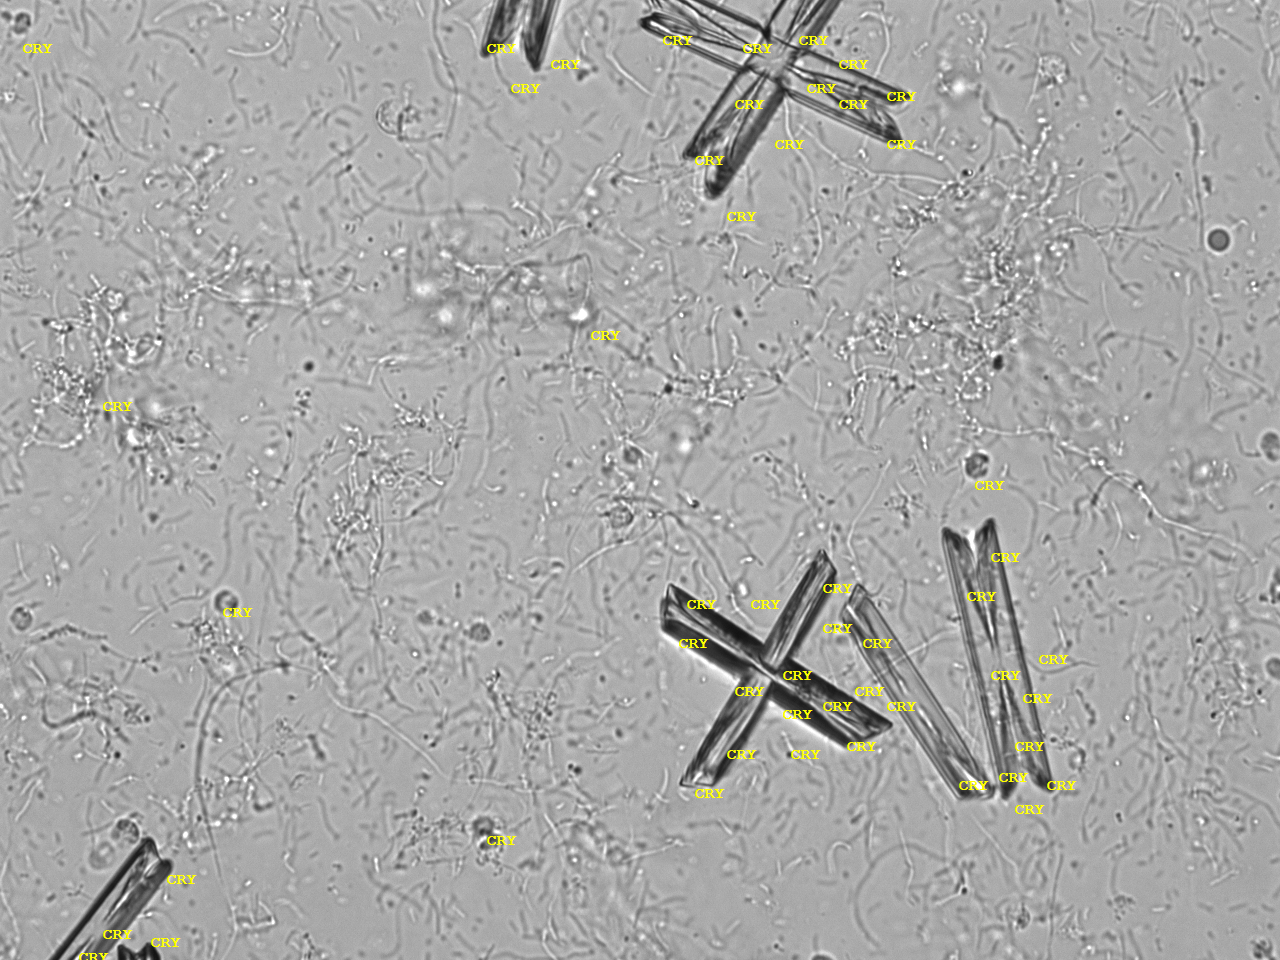

Urin-Feature: CaPhosphate